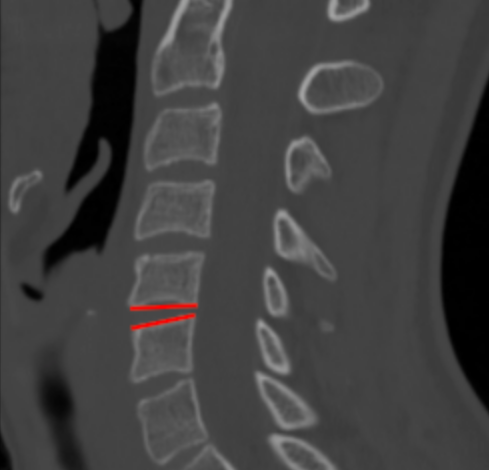

Image Type Cervical Spine X-Ray CT Scan MRI Scan Atlantodental Interval (ADI) Basion–Axial Interval (BAI) Basion–Dens Interval (BDI) Canal Occupying Ratio (COR) Clivo-Axial Angle Facet Joint Overlap (Percent Overlap Method) Facet Joint Step-Off/Dislocation Grabb-Oakes Measurement (pB - C2 line) Occipital Condyle–C1 Interval (CCI) Posterior Atlantodental Interval (PADI) Power’s Ratio Sagittal Vertical Axis (SVA) Segmental Angle Translation on Sagittal Reconstruction